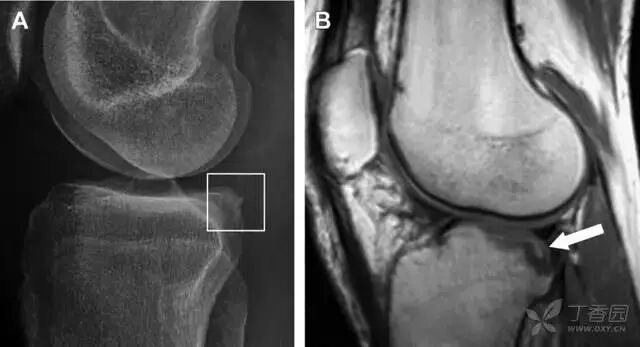

股骨外侧髁凹陷征(图 2)

图 2 扭伤后的股骨外侧髁凹陷征。A 侧位片示股骨外侧髁凹陷。B MRI 矢状位 T2 加权像示股骨外侧髁及胫骨后外侧骨挫伤(空箭头)。胫骨近端随着后交叉韧带撕裂发生移位,露出外侧半月板的后角(弧形箭头)

胫骨后外侧碎片骨折

胫骨后外侧小片骨皮质的压缩性骨折,可能是旋转移位损伤的唯一证据(图 3)。这种骨折在常规膝关节平片很难发现,若怀疑存在骨折,行下肢内旋斜位片检查可诊断。

图 3 胫骨后外侧碎片骨折。A 正位片示胫骨后外侧处可见一压缩骨折的小碎片(方框)。这是胫骨撞击股骨外侧髁旋转移位时所致。B 另一位患者的 MRI 矢状位 T1 加权像示胫骨后外侧骨折碎片(箭头)